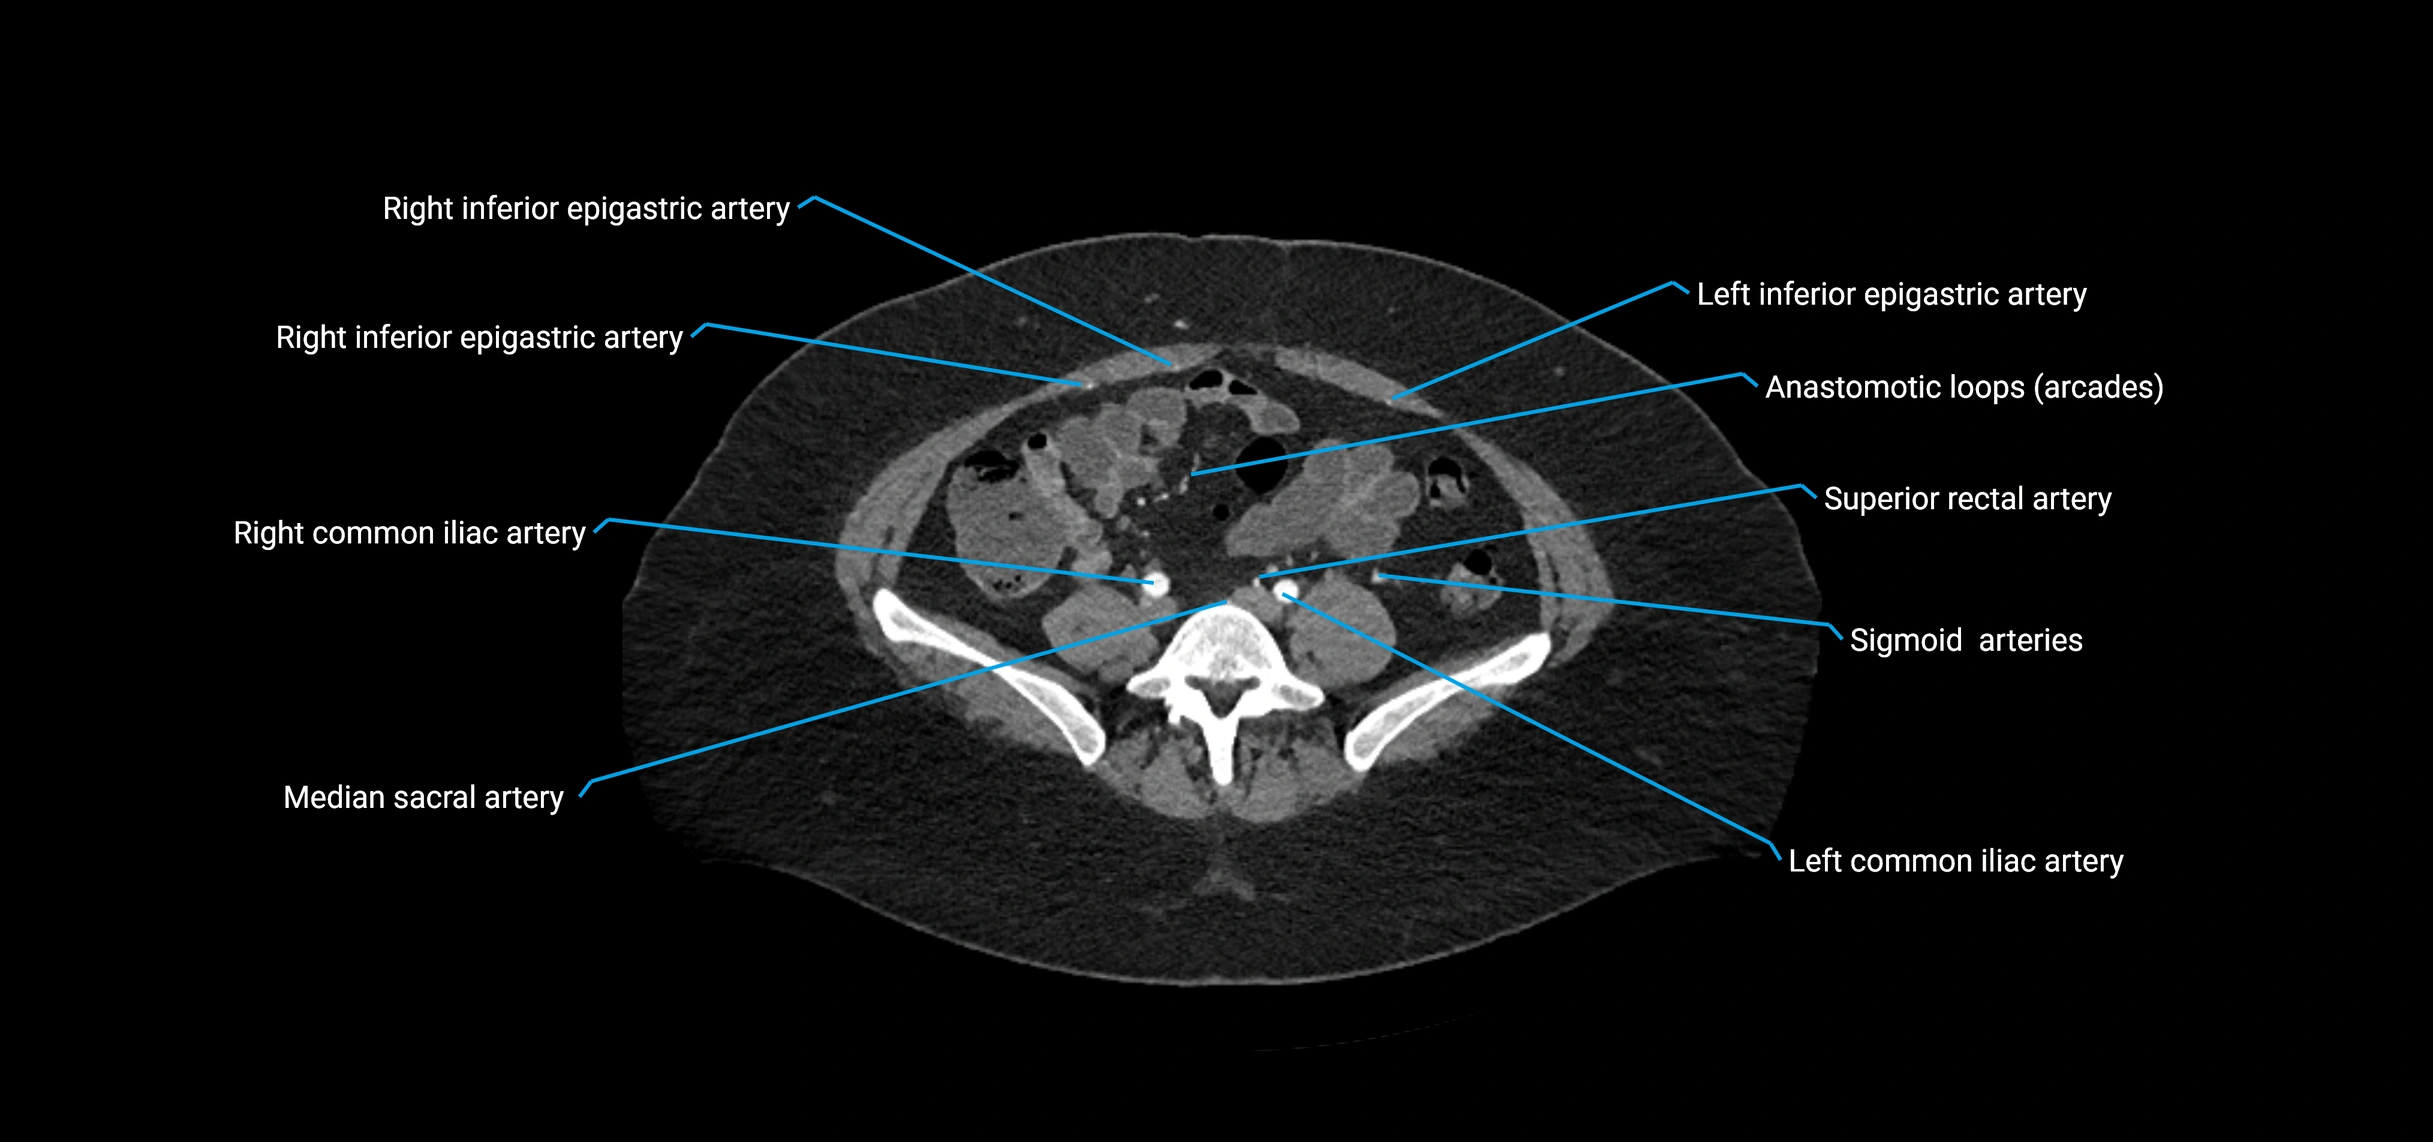

CT images

image

Contrast-enhanced CT (CTA):

• Gold standard for abdominal aortic imaging

• Provides excellent detail of lumen, wall, aneurysm, thrombus, and branch vessels

• Multiplanar and 3D reconstructions help in aneurysm measurement, stent graft planning, and dissection evaluation